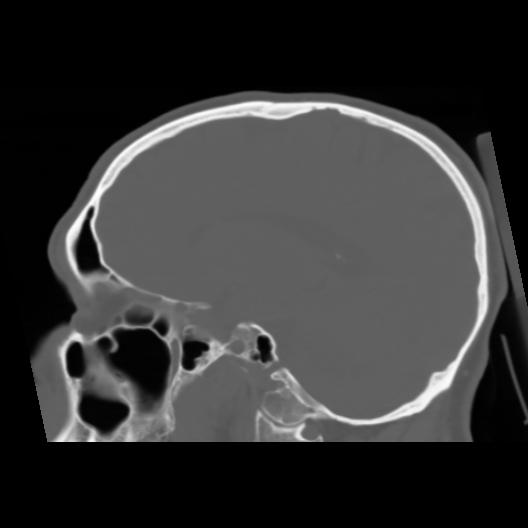

6 CEREBRO,,Sagittal,3.000,CEREBRO,Sagittal,